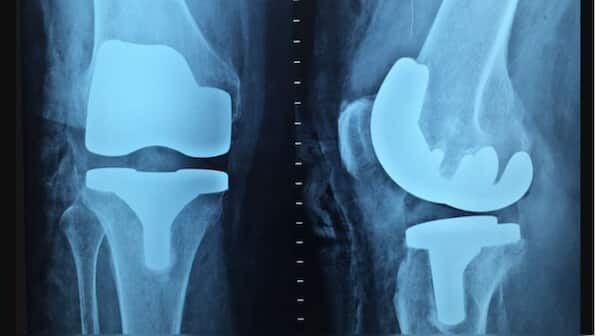

Osteoporosis has emerged as a significant public health concern in India, with alarming statistics revealing that approximately 61 million people are affected by the condition, of which 80 percent are women. According to the World Health Organization (WHO), 30 percent of postmenopausal women globally suffer from osteoporosis, highlighting a pressing issue that requires urgent attention.

Dr Chaudhry: Osteoporosis in simple terms is called hollowness or weakening of the bones or the skeletal system and it usually occurs most commonly in postmenopausal women and elderly males as well. Now, two major categories of osteoporosis one is senile osteoporosis other is postmenopausal osteoporosis, both are age related and also in females because of the menopause there is a sudden drop in estrogen level which is actually a protector of the bone hormone which protects the bone and because of its loss the first 5 years after the menopause it causes severe osteoporosis and it is a concern for public health because since being a silent disease it is not easily diagnosed and most of the people consider generalized weakness bone pains as age related and then it goes unnoticed until the terminal event of a major fracture or after a trivial injury happens and then that leads to catastrophic complications.

So, if you look at the data more than 50 years of age every other woman is suffering from osteoporosis of varying degree and most of them they end up having a fracture and out of 1 out of 4 males are also suffering from osteoporosis above 50 years of age. So, it is a quite a common problem and because of added deficiencies of calcium vitamin D it becomes more paramount to recognize early and treat it well.

Dr Chaudhry: Yes, women are more likely to get affected with osteoporosis almost as much as 2 times at higher risk wherein 1 in every 2nd woman gets osteoporosis beyond the age of 50 years like and whereas in men it is 1 in 4 people. And the major reason is the menopause which reduces the levels of estrogen which is a bone preserving hormone and thus because of sudden loss of estrogen there is a sudden spurt of bone loss and thus causes very severe osteoporosis in many females.